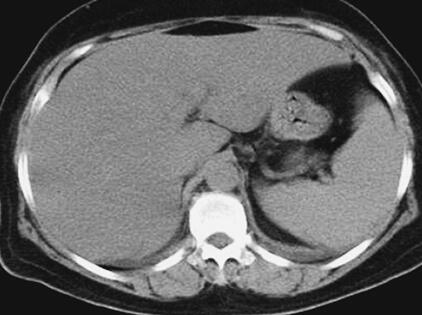

患者,女性,59岁。因“发热8天,上腹部隐痛、腹泻伴胸闷7天”于2011年7月8日入院。患者8天前出现发热,39.5℃,无畏寒、寒战,在当地卫生院予输液治疗(具体不详),症状未好转。7天前出现上腹部隐痛、腹泻,日约4~5次,黄色稀便,伴胸闷,遂就诊于当地镇医院,心电图检查正常,拟“中暑”,予针灸等治疗后无好转。2天前就诊于当地县人民医院,查血常规:WBC 8.4×109/L,N 89.2%,Hb 102g/L,PLT 92×109/L;肥达反应阴性;肝功能:ALT 104IU/L,AST 144IU/L,TP 55g/L,ALB 27g/L;腹部CT:脂肪肝,脾肿大;胸部CT:两肺少许炎症,左侧可疑少许胸腔积液,拟败血症,中毒性肝炎,伤寒住院治疗;期间体温波动于38~39℃,血压波动于80/50~90/60mmHg,予多巴胺[6.0μg/(kg·min)]升压,予亚胺培南-西司他汀钠联合头孢曲松抗感染治疗,病情无好转,仍有发热、腹泻、上腹部隐痛不适,并出现尿量减少、血肌酐升高。于7月8日转笔者医院急诊,测血压[多巴胺6.0μg/(kg·min)维持]89/55mmHg,血常规:WBC 10.28×109/L,N 89.4%;Lac 2.3mmol/L,CRP>90.0mg/L,Cr 141μmol/L,cTnI 6.02μg/L,BNP 577pg/ml;胸腹部CT:两下肺背侧散在炎症,两侧胸腔少量积液,慢肝样病变,胆囊结石(图1、图2);腹部B超:脂肪肝,脾偏大,拟发热待查,心肌炎?感染性休克?,予补液、亚胺培南-西司他汀钠控制感染,多巴胺升血压,为进一步治疗拟上述诊断收入急诊重症监护病房。既往史:40年前发现胆囊结石。

图2 胸腹部CT:脾肿大(7月8日)